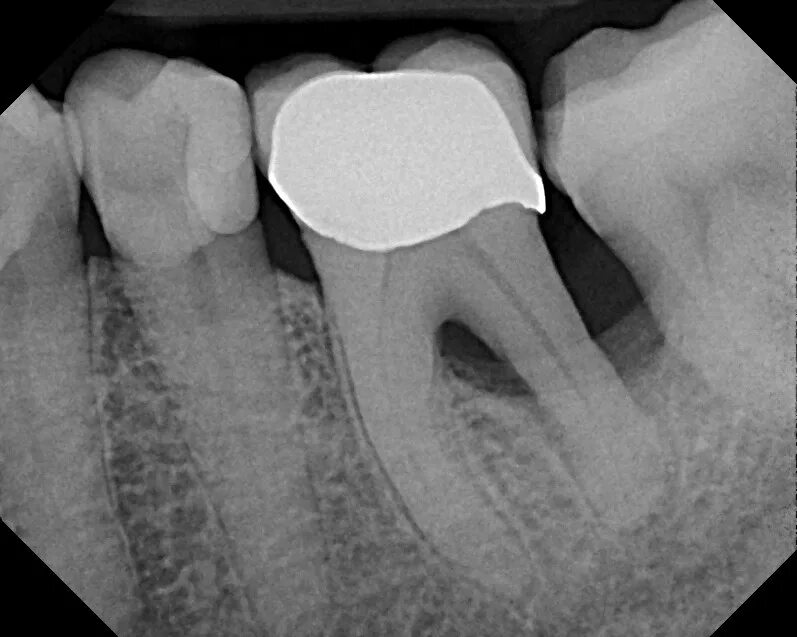

Зубной карман